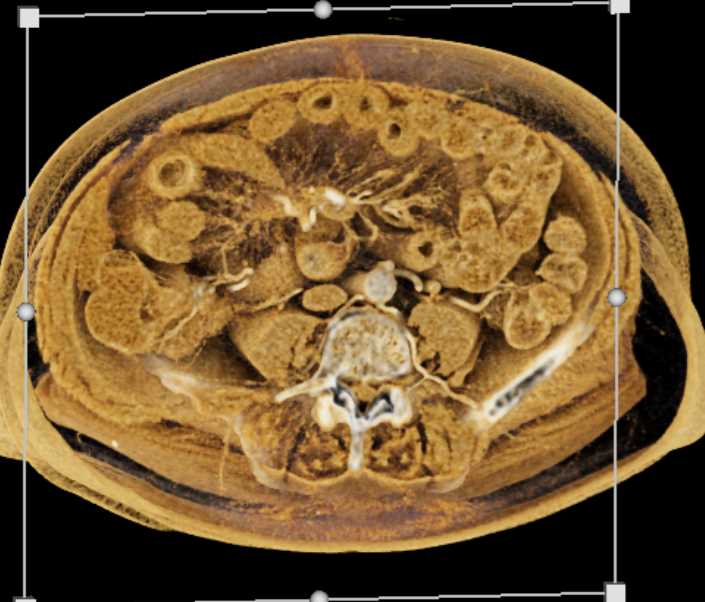

Intraluminal Mass with Intusuception RLQ